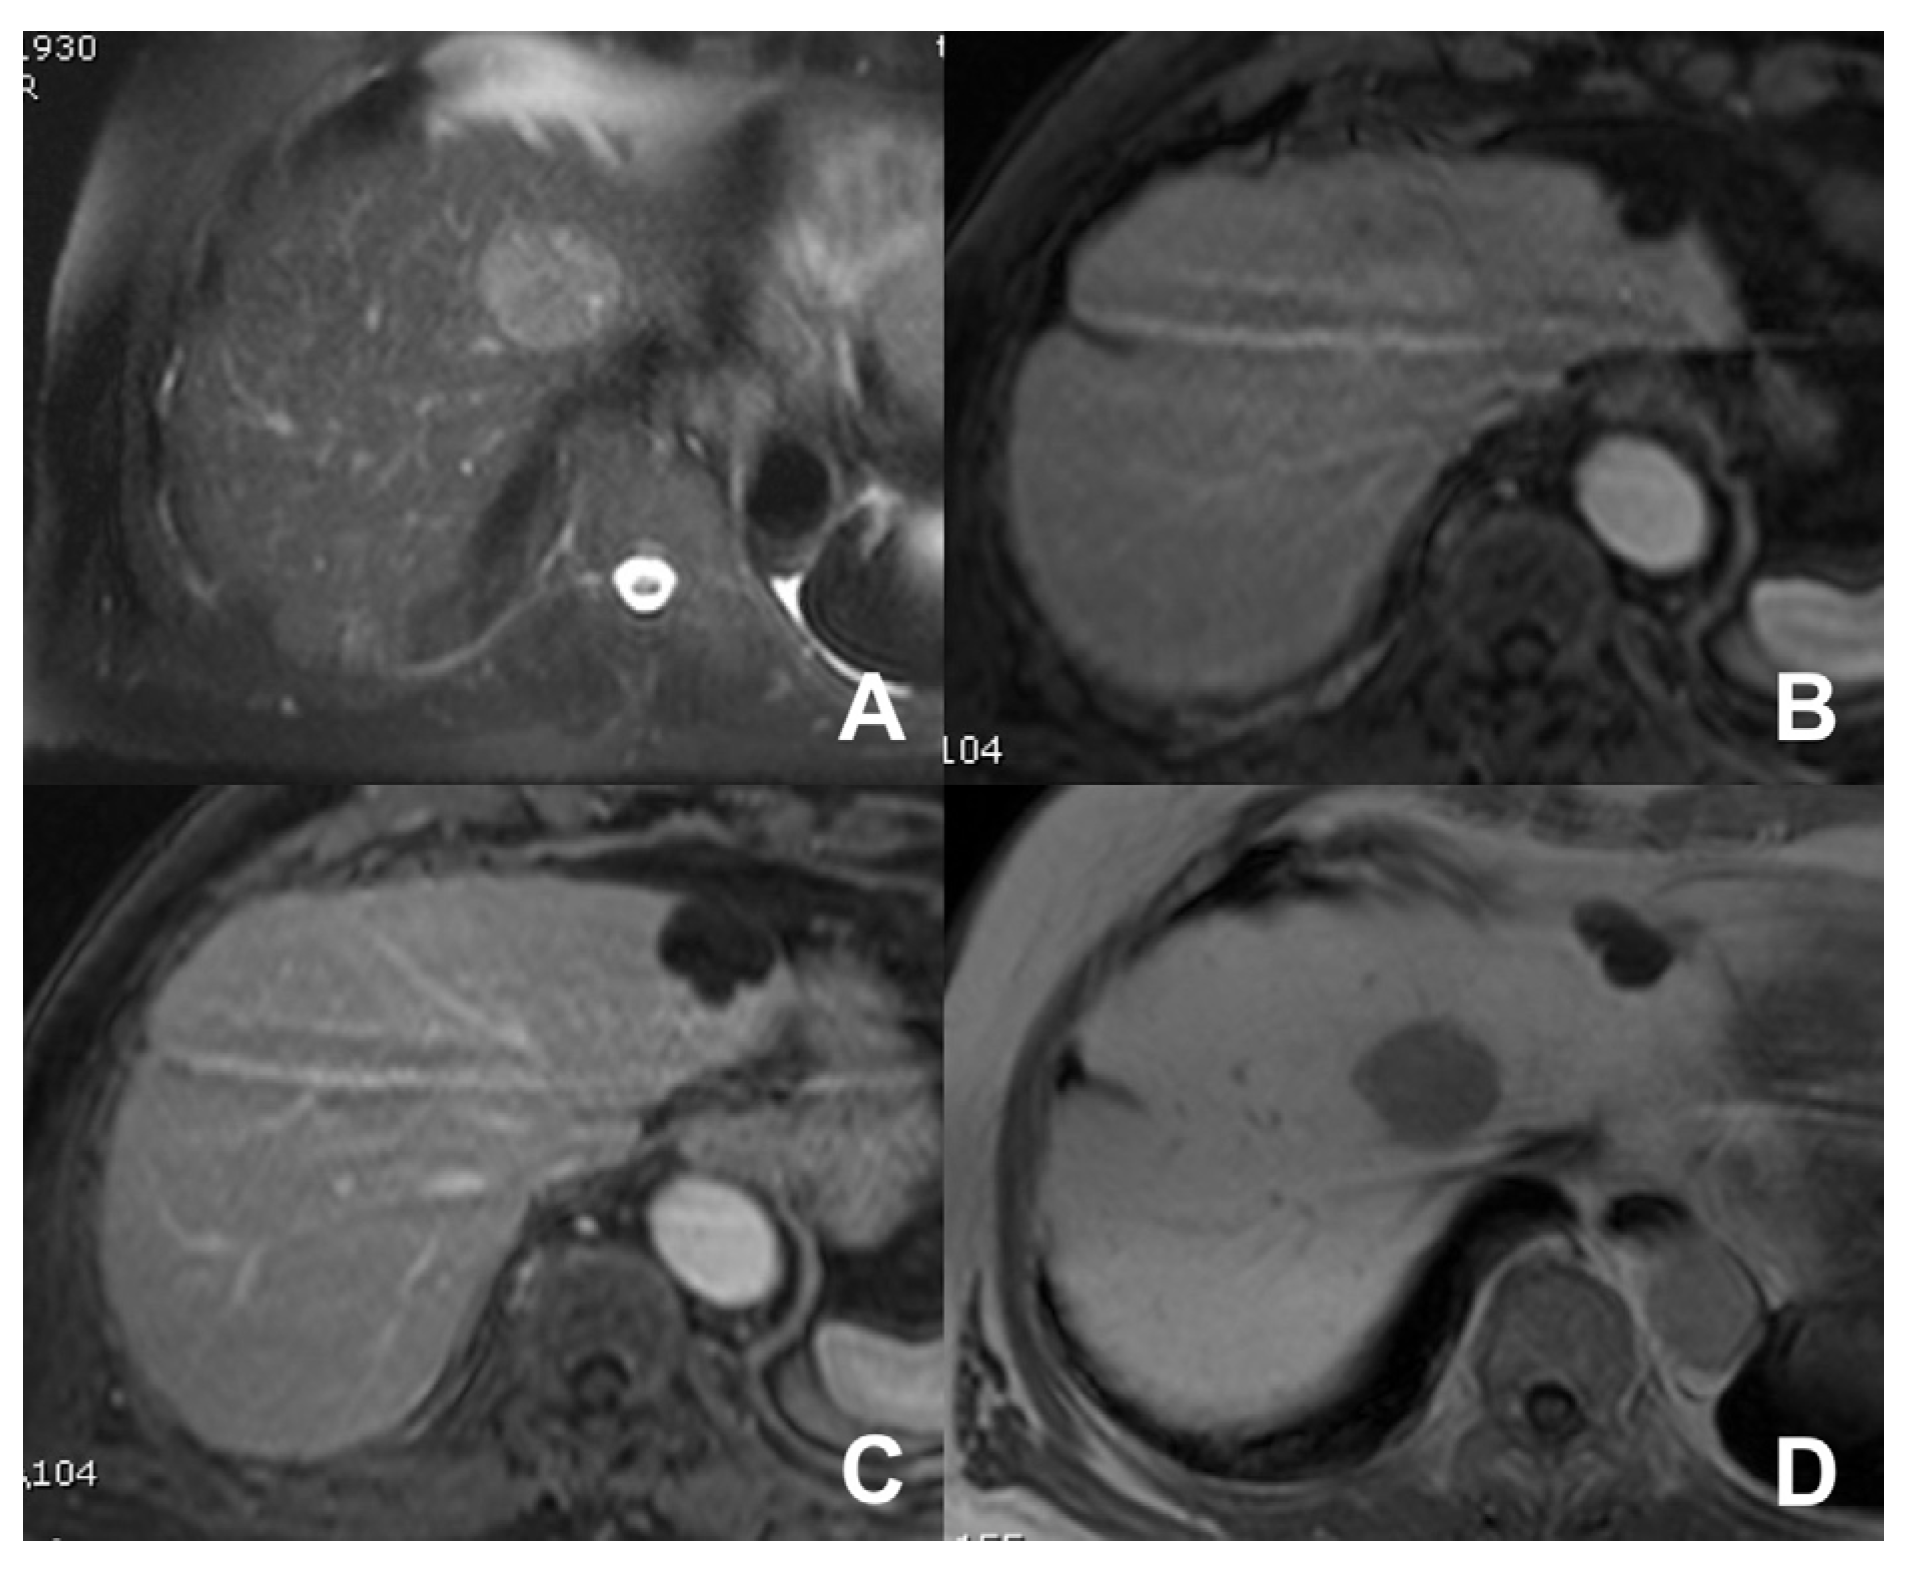

| GRE T1 3D DYNAMIC | AXIAL | PRE-ART 25″-PORTAL 70″-LATE 180″ | YES (if the lesion is hypervascular) | Benign hypervascular hepatocitic lesions appear hyperintense in HBP | |

| GRE T1 3D DYNAMIC | AXIAL | PRE-ART 25″-PORTAL 70″-LATE 180″ | YES (if the lesion shows atypical enhancement) | Hypointensity in HBP suspicious for HCC | |

- Grazioli, L.; Morana, G.; Federle, M.P.; Brancatelli, G.; Testoni, M.; Kirchin, M.A.; Menni, K.; Olivetti, L.; Nicoli, N.; Procacci, C. Focal nodular hyperplasia: Morphologic and functional information from MR imaging with gadobenate dimeglumine. Radiology 2001, 221, 731–739. [Google Scholar] [CrossRef] [PubMed]

- Grazioli, L.; Morana, G.; Kirchin, M.A.; Schneider, G. Accurate differentiation of focal nodular hyperplasia from hepatic adenoma at gadobenate dimeglumine-enhanced MR imaging: Prospective study. Radiology 2005, 236, 166–177. [Google Scholar] [CrossRef] [PubMed]

- Morana, G.; Grazioli, L.; Kirchin, M.A.; Bondioni, M.P.; Faccioli, N.; Guarise, A.; Schneider, G. Solid hypervascular liver lesions: Accurate identification of true benign lesions on enhanced dynamic and hepatobiliary phase magnetic resonance imaging after gadobenate dimeglumine administration. Investig. Radiol. 2011, 46, 225–239. [Google Scholar] [CrossRef] [PubMed]